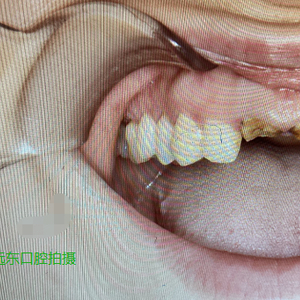

王女士的各项条件都比较好,所以进行的就是即刻种植,即拔完残根立即植入种植体,现在她只需要经过3-6个月达到骨结合后,再进行牙冠修复,大大缩短的治疗时间。虽然植入了种植体,在等待骨结合的这段时间王女士就得忍受没有门牙齿的不便和苦恼。

为了解决她的苦恼远东口腔科赵川医生为她进行了“即刻修复”,即制作一个临时牙冠修复门牙缺失,等过了骨结合期,届时取掉临时牙冠,装上种植牙的牙冠。这个临时牙冠虽然不能和真牙比,至少装上后能让王女士不必面对门牙缺失的尴尬。